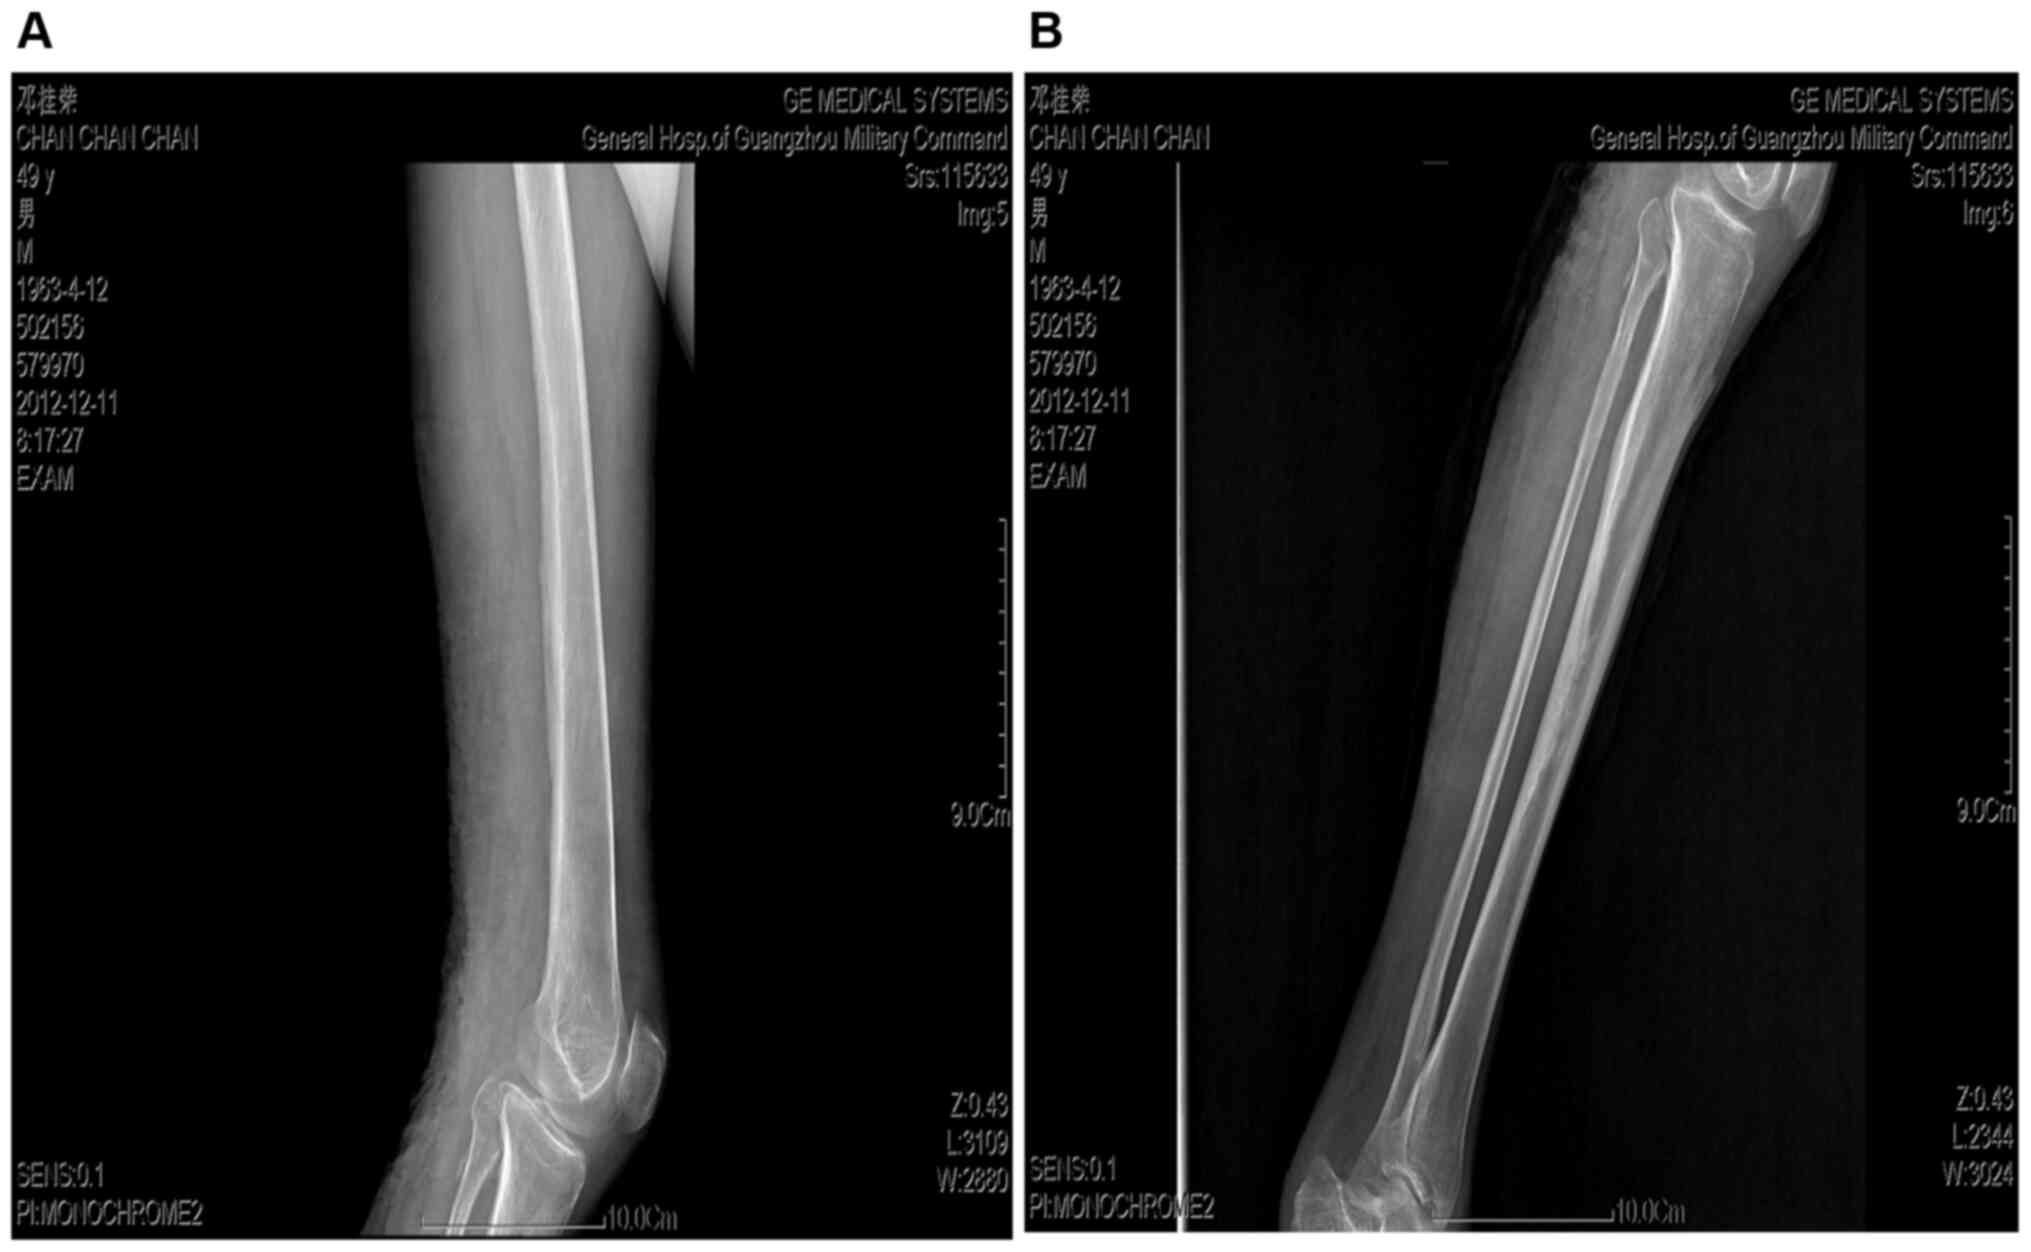

Following a dermatological examination, the patient was found to have an irregularly-shaped deep ulcer on the left lower extremity dorsum, which was approximately 36x16 cm. The wound granulation exhibited a cauliflower-like pattern, and a thick layer of necrotic material was observed. The edge of the ulcer was hard and everted, approximately 1 cm higher than the surrounding skin. A large amount of exudate was observed on the wound, and a foul odor was present. The left inguinal lymph nodes were enlarged. The size of the lower lymph node group was approximately 3x5 cm, and the upper group consisted of 5-6 lymph nodes of approximately 1x1 cm. The enlarged lymph nodes were somewhat hard, with no apparent tenderness, a low degree of activity, and no adhesion to the surrounding tissues. No bone tissue damage was detected on leg radiographs (Fig. 1). A biopsy of the ulcerative tissue (performed by a pathologist) revealed highly differentiated squamous cell carcinoma (Fig. 2).

Figure 1

Radiographs of the affected leg. No bone tissue damage could be detected on these images. (A) Left femur; (B) Left tibia and fibula.